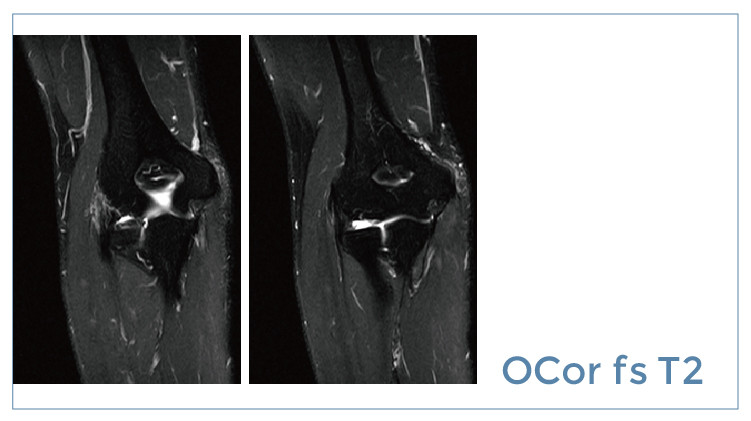

【朗润影像档案】20190726磁共振影像病例结果讨论

【朗润影像档案】磁共振影像病例分享(编号20190726)